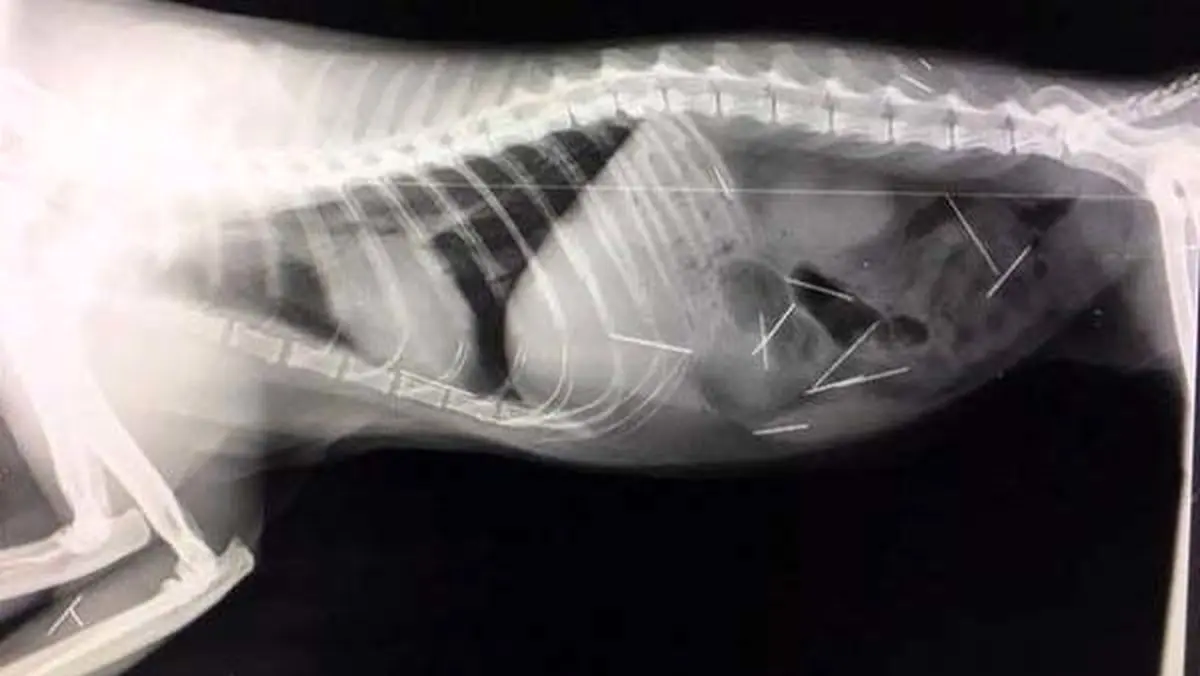

به همین دلیل به یک بیمارستان منتقل شد و متاسفانه نتایج سی تی اسکن، کمی هولناک و شوکه کننده بود! پزشکان در بدن او 31 سوزن کشف کردند و محققان بر این باور هستند که این سوزن ها توسط یک دستگاه به بدن او فرو رفته اند و قسمت بالای سوزن ها بصورت کامل بریده شده بودند.

با این وجود محققان بر این باور هستند که این امر توسط یک نفر انجام نشده است چرا که منیک می توانست فورا دست به فرار بگذارد و به همین دلیل بر این باور هستند که این اتفاق توسط چند نفر انجام شده است. به همین دلیل مالک او گفت باید افرادی که این کار را با منیک کرده اند فورا پیدا شوند.

سوزن هایی که با بی رحمی تمام وارد بدن منیک شده اند، هنوز منبعی اعلام نکرده است که توسط تیم پزشکی خارج شده اند یا خیر؟ و همچنین پلیس و خانواده منیک در حال جستجوی عوامل این اتفاق هستند.